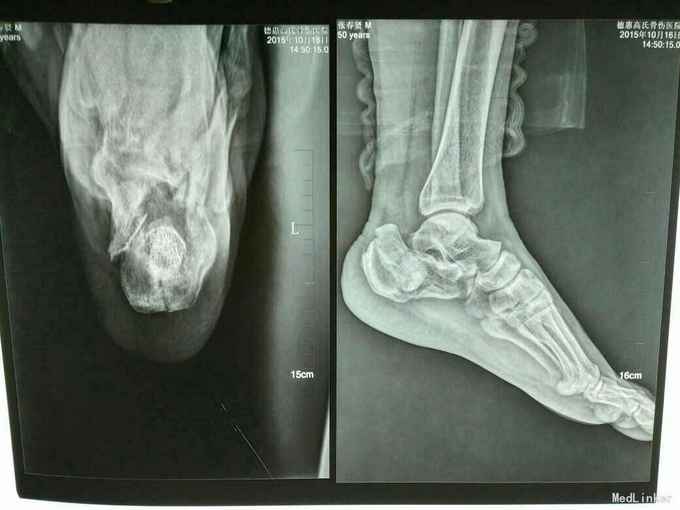

双足跟骨骨折

摔伤致双足跟部疼痛.肿胀.活动受限1小时

双足跟处肿胀,畸形明显,可触及骨擦感及异常活动,

双足跟骨骨折,手术治疗,

左足跟骨骨折